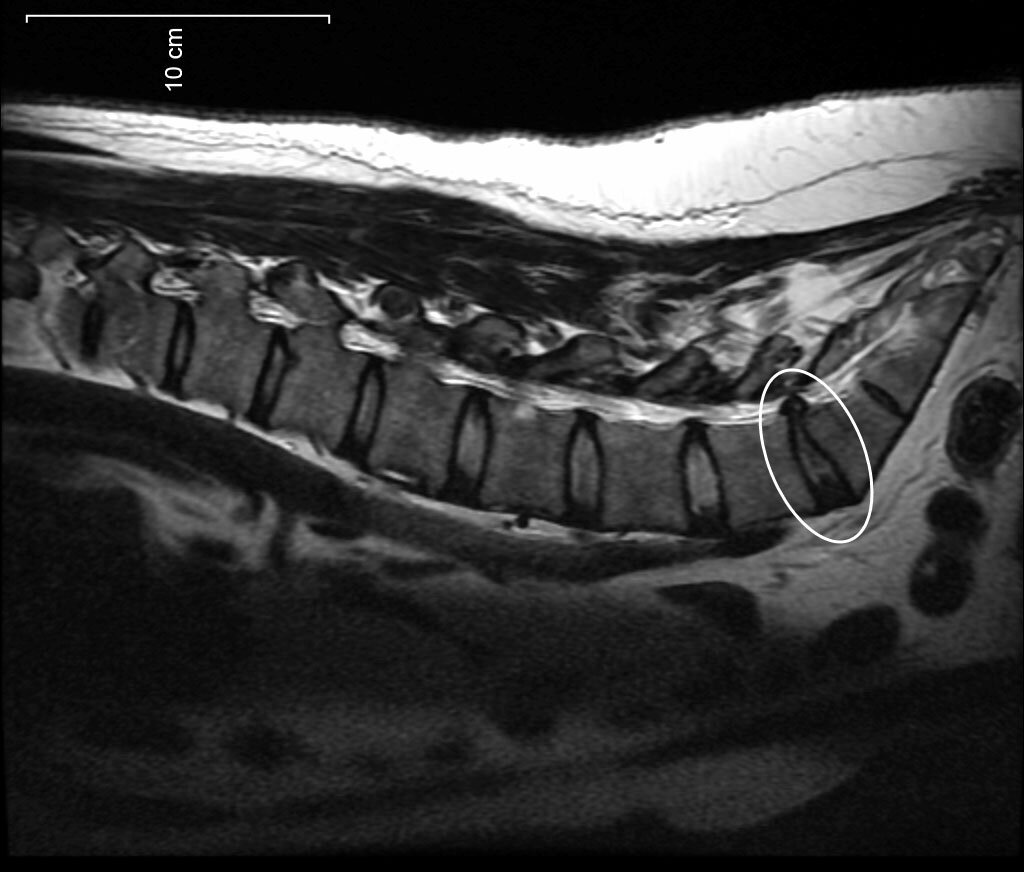

Видимая протрузия на снимке МРТ